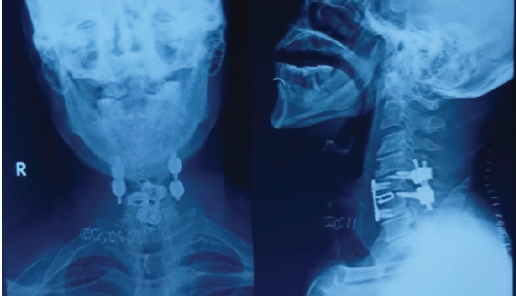

- Posterior lateral mass fixation for immediate stabilization (Fig. 6)

Figure 6: Post-operative cervical spine X-ray, anterior-posterior and lateral view showing the posterior cervical stabilization.

- Anterior cervical discectomy and fusion at the C5–C6 level to restore disc height and anterior column support (Fig. 7).

Figure 7: Post-operative cervical spine radiograph showing anterior-posterior and lateral views after the second procedure, showing anterior cervical discectomy and fusion at the C5–C6 level.